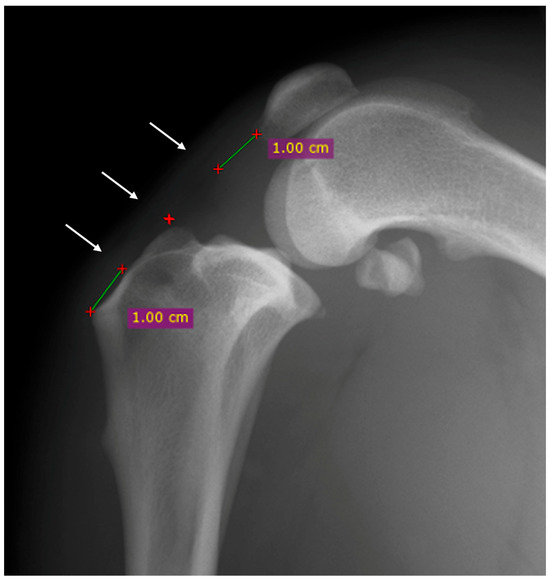

2.3. Radiographic Evaluation

3.2. Radiographic and Ultrasonographic Evaluations